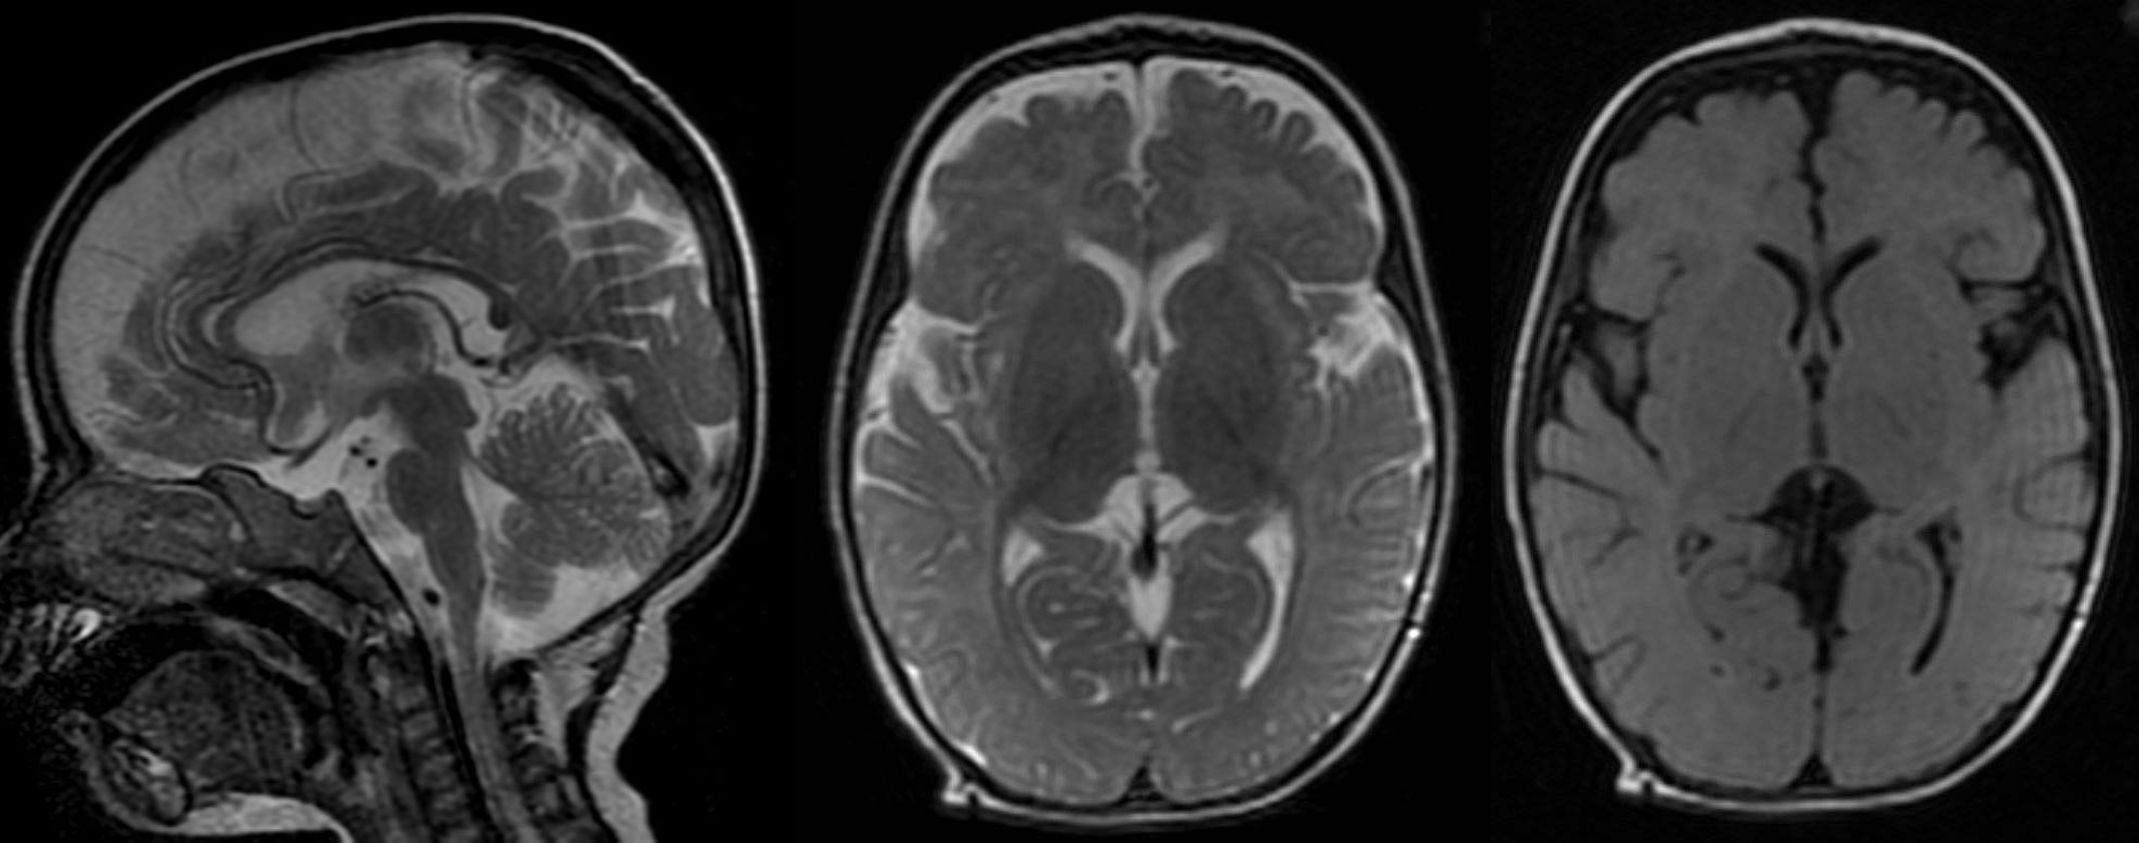

T2W sagittal, axial FLAIR and T2W sequence revealing diffuse atrophy and reduced volume of corpus callosum. Hyperintensity on T2W sequence suggestive of marginally poor myelination.

Non specific cerebral atrophy of different grades was observed in all cases except one. In [Table/Fig-2], reduced thickness of corpus callosum was observed in six patients on MRI brain studies. ITS cases who had severe wasting, three out of four showed evidence of cerebral atrophy; all three children with moderate wasting had evidence of cerebral atrophy. Cerebral atrophy was observed in all children with stunting as well as in children having normal height for age and sex. Some patients (6/10) had mild to moderate ventricular dilatation and most patients (9/10) had prominence of Sylvian sulcus. Ventricular dilatation and prominence of Sylvian sulcus had correlation with the grades of cerebral atrophy in all cases [Table/Fig-3,4,5,6,7,8,9,10,11 and 12].